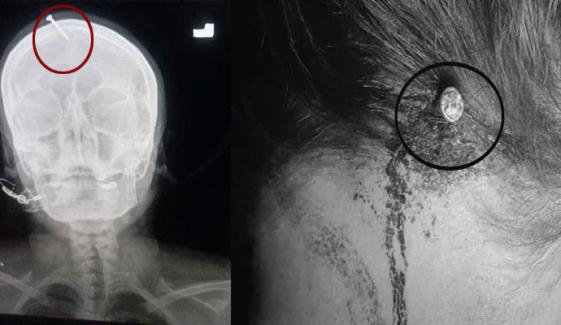

واضح رہے کہ متاثرہ خاتون کی 3 بیٹیاں ہیں اور نرینہ اولاد نہیں ہے، خاتون کے شوہر کو بیٹیاں پسند نہیں تھیں، بیٹے کی پیدائش کی خواہش پر جعلی عامل کے کہنے پر خاتون کے سر میں کیل ٹھونکی گئی تھی۔

متاثرہ خاتون کو علاج کے لیے لیڈی ریڈنگ اسپتال لایا گیا تھا، اسپتال کے نیورو سرجن ڈاکٹر حیدر نے بتایا کہ خاتون حاملہ تھی اور اس کے سر پر گہری چوٹ آئی تھی، کیل کو سرجری کر کے نکال دیا گیا اور خاتون کو ڈسچارج کر کے گھر روانہ کر دیا گیا تھا۔

ڈاکٹروں نے پولیس کو اطلاع دیے بغیر سرجری کر کے خاتون کے سر سے کیل نکال دی، اسپتال ریکارڈ میں میاں بیوی کا شناختی کارڈ نمبر تک نہیں رکھا گیا۔